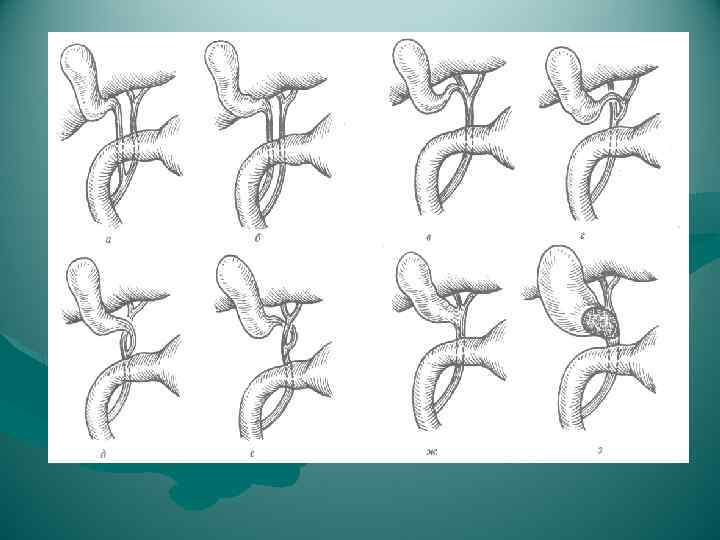

а) Типичное кровоснабжение; б) правая печеночная артерия, исходящая из верхней брыжеечной артерии, в) добавочная левая печеночная артерия, исходящая из левой желудочной артерии; г) сразу же после отхождения от чревного ствола общая печеночная артерия делится на правую и левую ветви, которые проходят друг возле друга, достигая печени через печеночно-двенадцатиперстную связку; д) правая печеночная артерия пересекает общий печеночный проток не сзади, а спереди; е) две пузырных артерии исходят от правой печеночной артерии; ж) пузырная артерия отходит от общей печеночной артерии и пересекает желчный проток не сзади, а спереди; з) пузырная артерия исходит из левой печеночной артерии и пересекает желчный проток спереди; и) имеются две пузырных артерии: одна отходит, как правило, от правой печеночной артерии и достигает желчного пузыря, пересекая общий желчный проток, как и в норме, сзади, тогда как другая пузырная артерия чаще всего отходит от общего ствола печеночной артерии (или от одного из ее стволов) и пересекает общий желчный проток спереди; к) пузырная артерия отходит от левой стороны правой печеночной артерии, при этом оба сосуда образуют петлю; если пузырную артерию перевязать в глубине, то в этом случае в лигатуру может легко попасть и правая печеночная артерия

а) Типичное кровоснабжение; б) правая печеночная артерия, исходящая из верхней брыжеечной артерии, в) добавочная левая печеночная артерия, исходящая из левой желудочной артерии; г) сразу же после отхождения от чревного ствола общая печеночная артерия делится на правую и левую ветви, которые проходят друг возле друга, достигая печени через печеночно-двенадцатиперстную связку; д) правая печеночная артерия пересекает общий печеночный проток не сзади, а спереди; е) две пузырных артерии исходят от правой печеночной артерии; ж) пузырная артерия отходит от общей печеночной артерии и пересекает желчный проток не сзади, а спереди; з) пузырная артерия исходит из левой печеночной артерии и пересекает желчный проток спереди; и) имеются две пузырных артерии: одна отходит, как правило, от правой печеночной артерии и достигает желчного пузыря, пересекая общий желчный проток, как и в норме, сзади, тогда как другая пузырная артерия чаще всего отходит от общего ствола печеночной артерии (или от одного из ее стволов) и пересекает общий желчный проток спереди; к) пузырная артерия отходит от левой стороны правой печеночной артерии, при этом оба сосуда образуют петлю; если пузырную артерию перевязать в глубине, то в этом случае в лигатуру может легко попасть и правая печеночная артерия